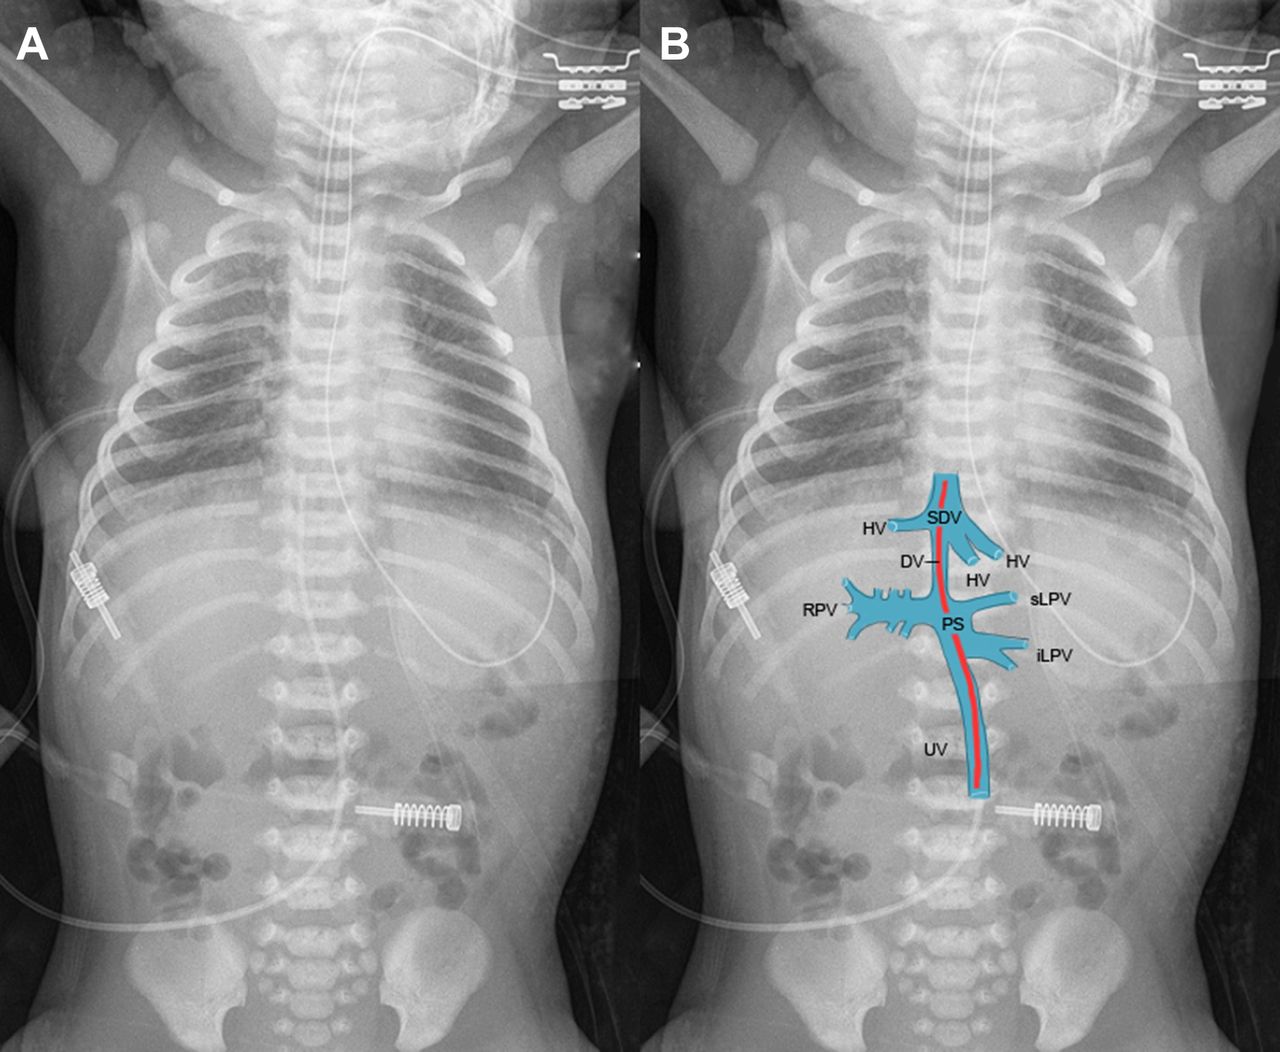

Learn about the risks, causes, and emergency management of a prolapsed umbilical cord. This critical obstetric complication requires immediate medical intervention to ensure fetal safety. Discover how healthcare providers diagnose cord prolapse, the importance of prompt delivery techniques, and essential steps taken during labor to prevent serious birth injuries and improve neonatal outcomes during this emergency.

Read full article: Prolapsed Umbilical Cord